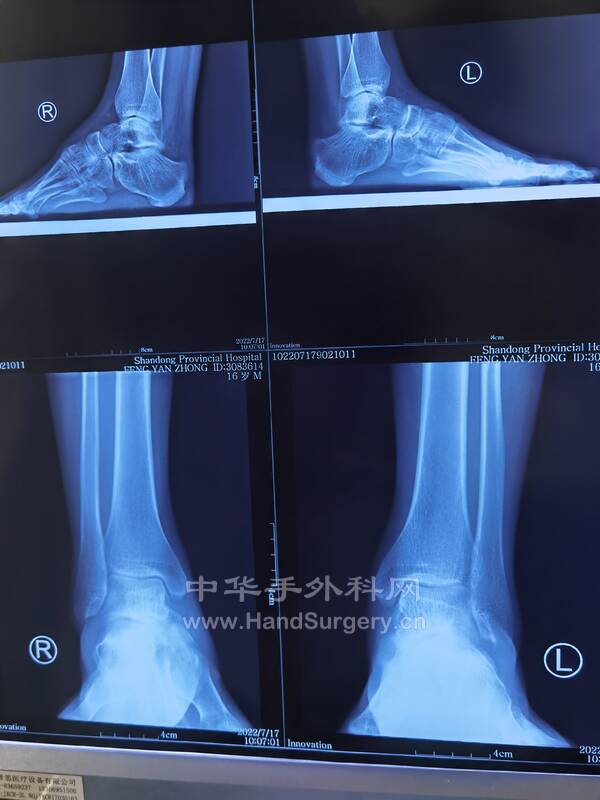

2.三代遗传的马蹄足患者,今日手术(见图),术式:经皮跟腱延长术,跖筋膜松解术,胫前肌腱1/2转位术,跟骨截骨外移术,第一跖骨上抬术,组合式外固定架固定术

1.男,16岁双足马蹄足,儿麻后遗症,偏瘫,可行手术治疗(图1-5)

马蹄内翻足患者DR片:

双足正侧位(负重位),双踝正侧位(负重位),双下肢全长正位,双跟骨轴位